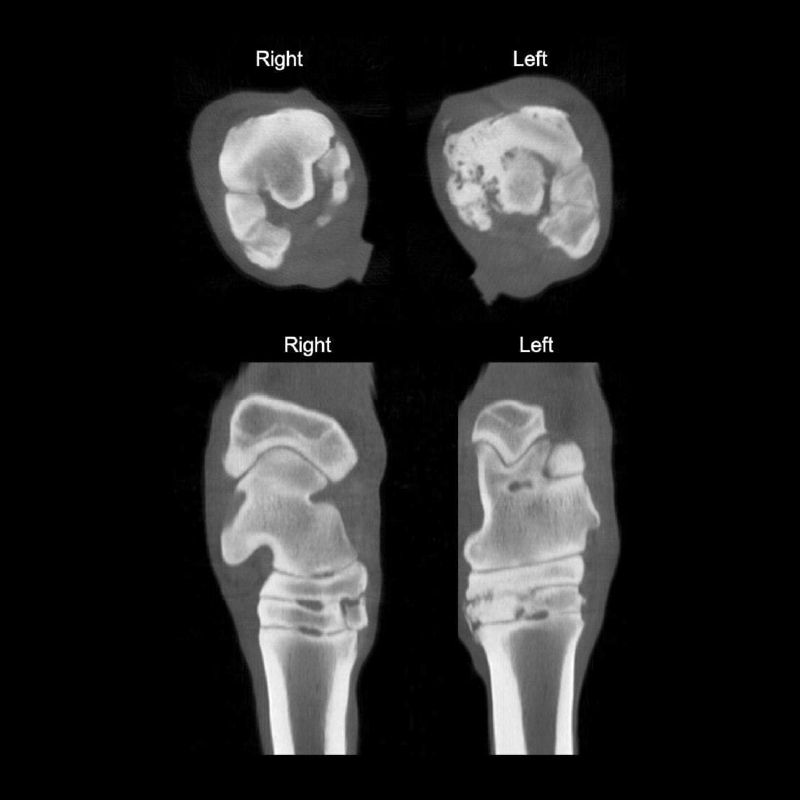

T.A.C – Tomografía Axial Computarizada

Pegasus Cone Beam CT

Tomografía Computarizada (TC)

En nuestro Centro, gracias al Equipo Pegasus TC, ofrecemos dos modalidades técnicas de exploración: TC multicorte y TC de haz cónico, permitiendo adaptarnos a las necesidades diagnósticas de cada paciente.

Esta tecnología proporciona una visualización altamente detallada de estructuras óseas y tejidos blandos en múltiples regiones del caballo: extremidades, babilla, codo, cabeza y cuello.

La tomografía computarizada de extremidades es especialmente útil para diagnosticar múltiples problemas ortopédicos en una misma zona, aportando una visión integral del daño.

Mediante la administración de contraste (CECT) es posible evaluar la actividad de lesiones de tejidos blandos y determinar la extensión del daño en el cartílago, algo que no se puede valorar con otras técnicas de imagen.